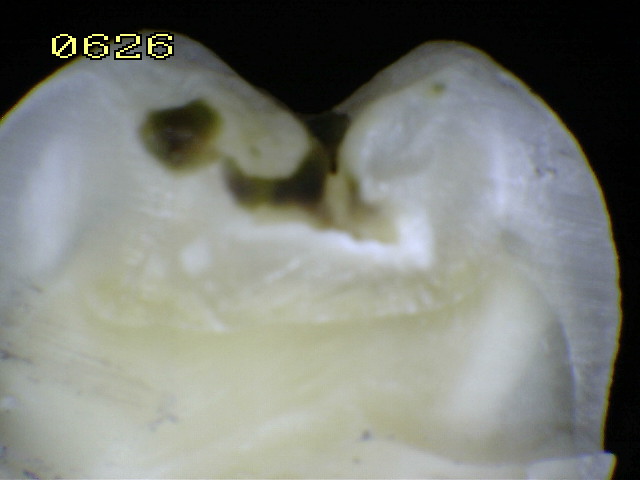

Espécimen Nº 27 |

Sección vertical por la línea celeste |

En el primer

y segundo recuadro micro-cavidades en esmalte

y caries dentinaria poco profunda. Se verifica un código 2

histológico. |